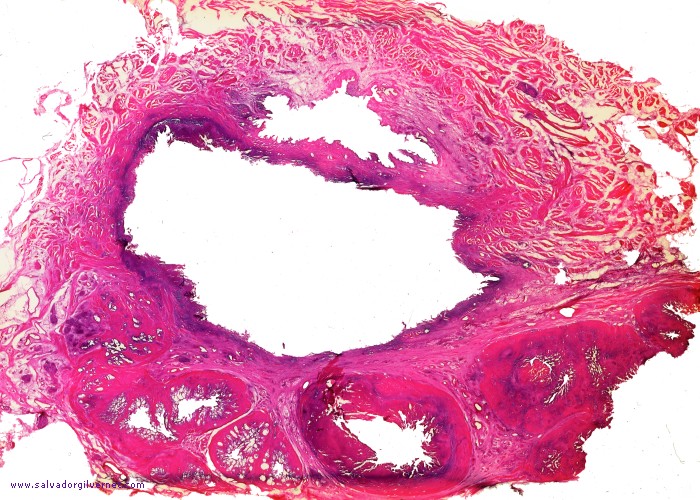

Detalle 1: Ampolla deferencial izquierda (flechas blancas) y ampolla y vesícula seminal derecha con cambios de fibroesclerosis tuberculosa (flechas negras)

• Sección transversal a nivel del cuello vesical. Caverna tuberculosa en el espacio intervesicogenital con la mucosa trigonal separando la caverna del cuello vesical. Ampolla y vesículas seminales derechas tuberculizadas (Detalle 1), siendo normales las contralaterales

Paciente de 43 años

Tinción HE

• ca. 1950

• Nota: Corresponde a la microfotografía de la figura 792 en la página 1373 de Enfermedades de la Próstata. Ed. Paz-Montalvo. Madrid, 1955.